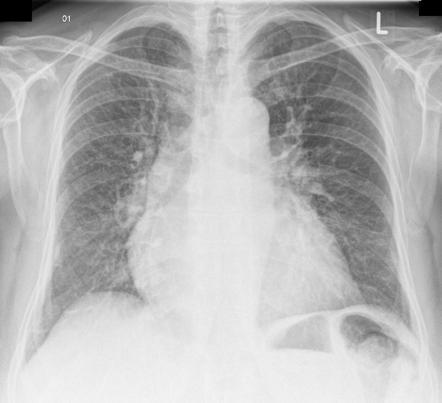

HF CXR sign

A= Alveolar oedema, classically this is perihilar ‘bat’s wing’ shadowing.

B= Kerley B lines—now known as septal lines. These are variously attributed to interstitial oedema and engorged peripheral lym- phatics.

C= Cardiomegaly—cardiothoracic ratio >50% on a PA film.

D= Dilated prominent upper lobe veins (upper lobe diversion).

E= Pleural Effusions.

Other features include peribronchial cuffing (thickened bronchial walls) and fluid in the fissures. (b) ‘Bat’s wing’, peri-hilar pulmonary oedema indicating heart failure and fluid overload.

Perihilar edema